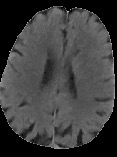

Accurate infarct segmentation in non-contrast CT (NCCT) images is a crucial step toward computer-aided acute ischemic stroke (AIS) assessment. In clinical practice, bilateral symmetric comparison of brain hemispheres is usually used to locate pathological abnormalities. Recent research has explored asymmetries to assist with AIS segmentation. However, most previous symmetry-based work mixed different types of asymmetries when evaluating their contribution to AIS. In this paper, we propose a novel Asymmetry Disentanglement Network (ADN) to automatically separate pathological asymmetries and intrinsic anatomical asymmetries in NCCTs for more effective and interpretable AIS segmentation. ADN first performs asymmetry disentanglement based on input NCCTs, which produces different types of 3D asymmetry maps. Then a synthetic, intrinsic-asymmetry-compensated and pathology-asymmetry-salient NCCT volume is generated and later used as input to a segmentation network. The training of ADN incorporates domain knowledge and adopts a tissue-type aware regularization loss function to encourage clinically-meaningful pathological asymmetry extraction. Coupled with an unsupervised 3D transformation network, ADN achieves state-of-the-art AIS segmentation performance on a public NCCT dataset. In addition to the superior performance, we believe the learned clinically-interpretable asymmetry maps can also provide insights towards a better understanding of AIS assessment. Our code is available at https://github.com/nihaomiao/MICCAI22_ADN.